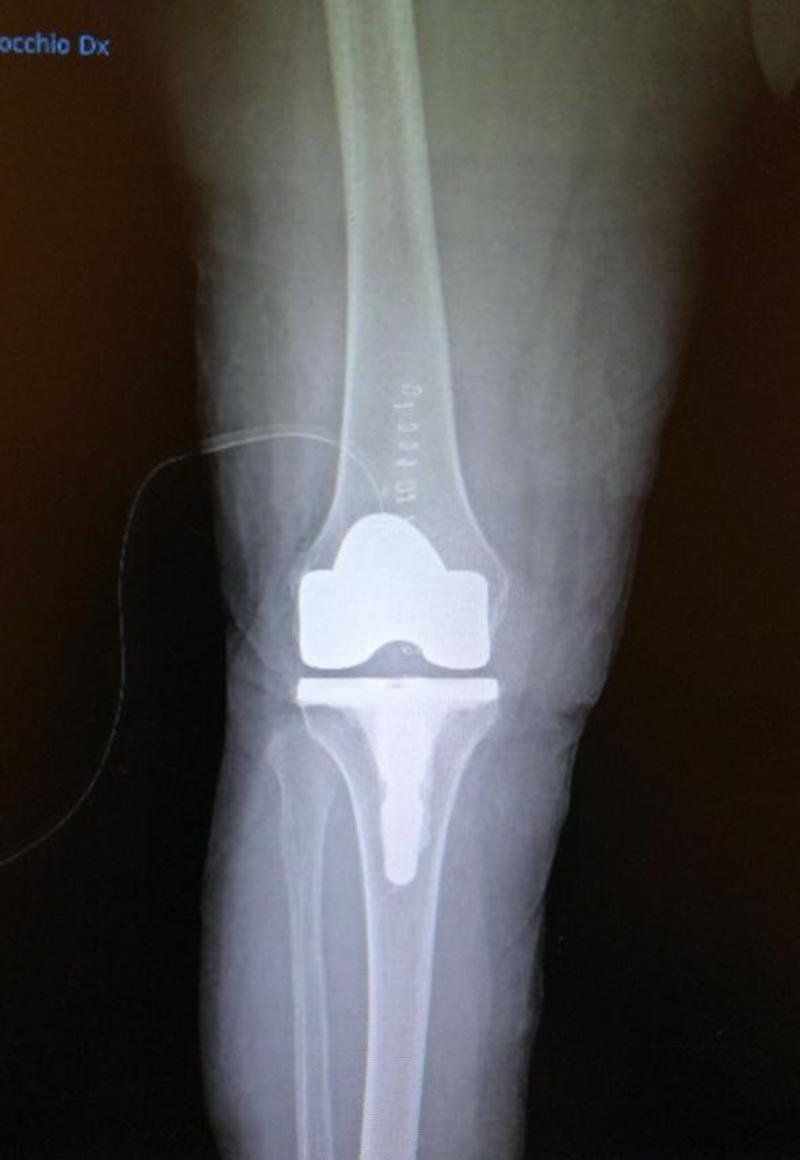

• Protesi ginocchio

• Protesi di ginocchio